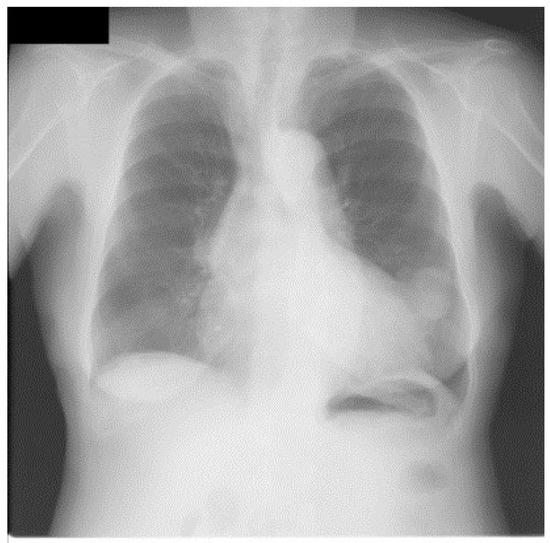

We also applied our method for the JSRT database in a similar manner for that of the portble CXRs database. Figure 7 shows an original image from JSRT database. We can see from Figure 8a that much more noise was created in the unsharp mask by using the Gaussian kernel. The EMEE value for the original CXR was 1.453. Although the EMEE value was improved to 5.643 for the final enhancement image, the noise in Figure 8a was also added in the final enhancement.

Figure 3. An image from portable chest radiograph (CXRs) database.